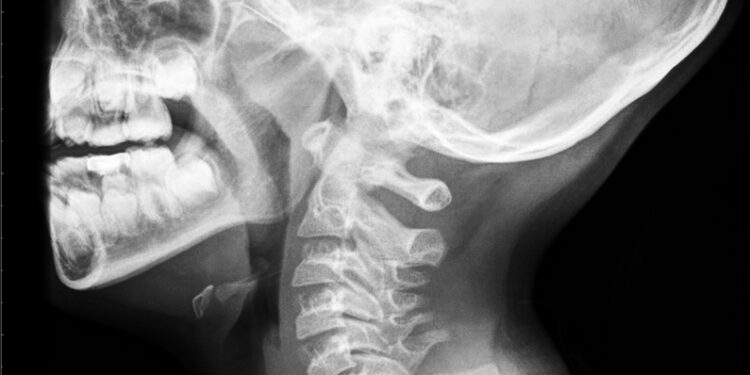

- Rentgeno nuotraukos padeda atskleisti sulipusius slankstelius, stuburo kreivumą ar kitus pakitimus

- Kartais prireikia kompiuterinės tomografijos (KT), jei reikia tikslesnės informacijos apie slankstelių struktūrą

- Magnetinio rezonanso tomografija (MRT) leidžia įvertinti minkštuosius audinius, diskus, nervų šakneles ir stuburo smegenis, padeda nustatyti ir kitus vidaus organų pokyčius